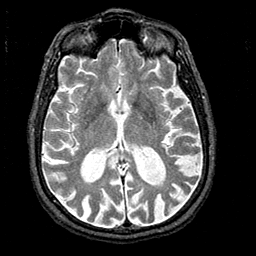

Alzheimer's disease MR T2-weighted -- Slice #25

[Home][Help][Clinical][Tour 1][Tour 2] Slice 25